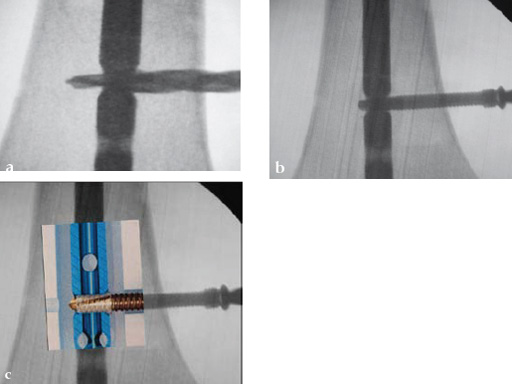

Drilling is identical but the near cortex needs additional reaming so it is wide enough to insert the sleeve. The enlarged hole at the near cortex will be filled by the thicker part which has a larger diameter than the rest of the screw (Fig 2). Use of the hand reamer has proven to be more tactile compared to drilling with machines (Fig 3). Power-driven drilling is only needed for very strong cortices, eg, the femur.

The sleeve is threaded on the screw by hand just before implantation (Fig 5). The lip of the sleeve needs to face the screw head. The sleeve is positioned correctly when the gold part of the screw is visible on either side of the sleeve (Fig 6). If the sleeve is placed too far on the screw, the connecting bars may be damaged or break. In this case a new sleeve has to be used. A sleeve with broken bars will not work. A sleeve positioner is available which prevents overthreading (Fig 7).

The screw-sleeve construct is pushed into the nail's locking hole by hand. For the final placement, a light hammer (100 gr) may be used (Fig 8). You can actually feel and even hear the correct positioning. Use of a heavier hammer may lead to too deep placement or even pushing the sleeve too far through the locking hole. Control by image intensifier of the reamer and/or screw placement is only needed in the very early part of the learning curve (Fig 9).

The final screw positioning can be felt as the broader screw thread widens the sleeve, filling up the enlarged near cortex.